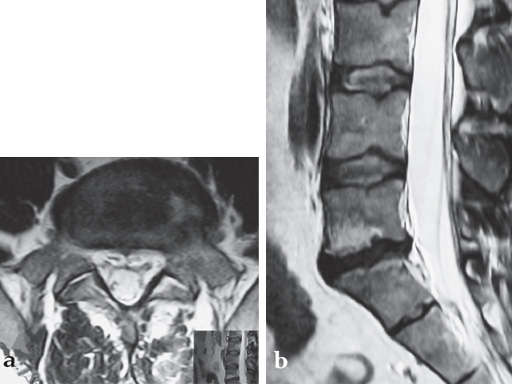

A 37-year-old female (65 kg and 170 cm tall) who suffered from back (L5/S1) and leg pain without neural compression for 2.5 years. She had a full range of conservative treatment and rehabilitation without benefit and reports a significant improvement in symptoms and function following surgery. She has returned to work with minimal restrictions in ongoing activities.

Intraoperative pictures.